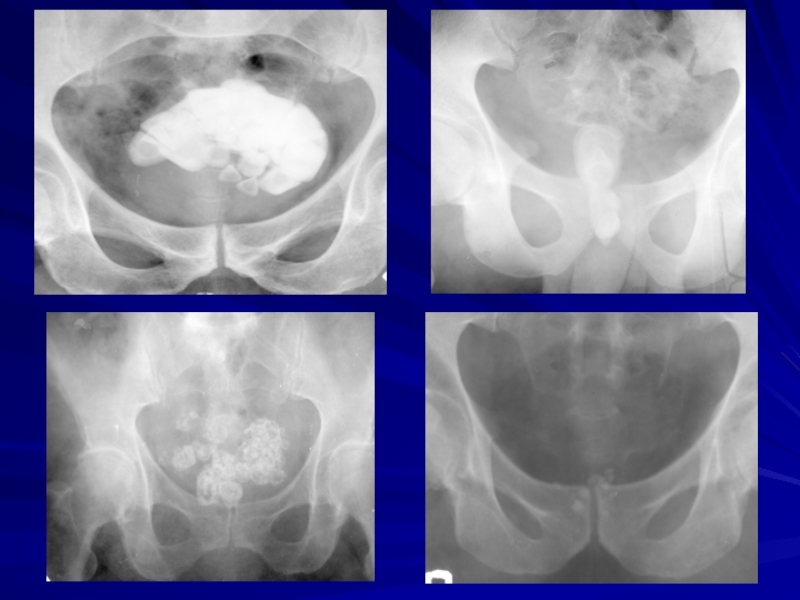

Расположение камней

Почки 50%

Верхняя чашечка 10%

Средняя чашечка 20%

Нижняя чашечка 60%

Почечная лоханка 10%

Мочеточник 40%

Верхний отдел 40%

Средний 40%

Нижний 20%

Мочевой пузырь 10%*